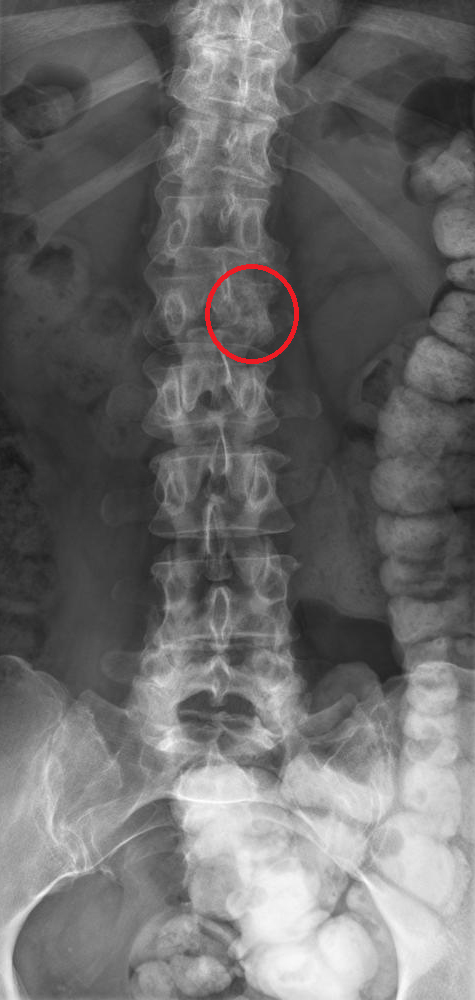

Son médecin traitant lui a prescrit de faibles doses de morphine, ce qui la soulage, et a fait réaliser l’élément suivant.

Question 11 - Concernant le tableau de la patiente (une ou plusieurs réponses exactes) :

Il s’agit d’un effet indésirable connu des inhibiteurs de l’aromatase, mais la perte du pédicule latéral gauche de L2 (vertèbre borgne) est en faveur d’une récidive.

L’aspect de vertèbre borgne est hautement évocateur d’une récidive (envahissement du pédicule latéral).

L’aspect de vertèbre borgne est fortement évocateur d’une récidive tumorale.